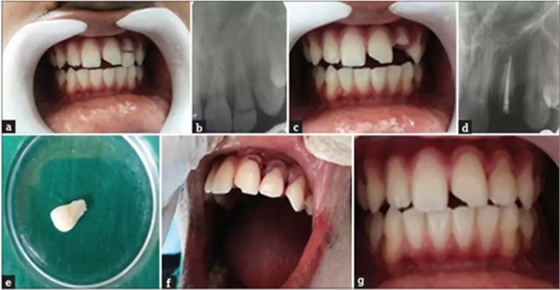

病例2

患者,男,19岁,因骑车发生事故导致上颌中切牙外伤。口腔检查可见牙齿22牙冠冠部EllisⅢ级牙折,从牙冠的牙冠中1/3到舌侧龈下2mm处。将牙齿折断部分无创地取出并储存在生理盐水中,完成根管治疗。如前所述,使用双固化树脂粘结剂通过合适的纤维桩将折断部分的牙折片与剩余的牙齿部分重新连接。最后,复位皮瓣,缝合。

a. 术前口内照片;b. 术前根尖片;c. 拔除牙齿折断片;d. 根管充填;e. 牙齿折断片;f. 折断片再复位;g. 术后2年。